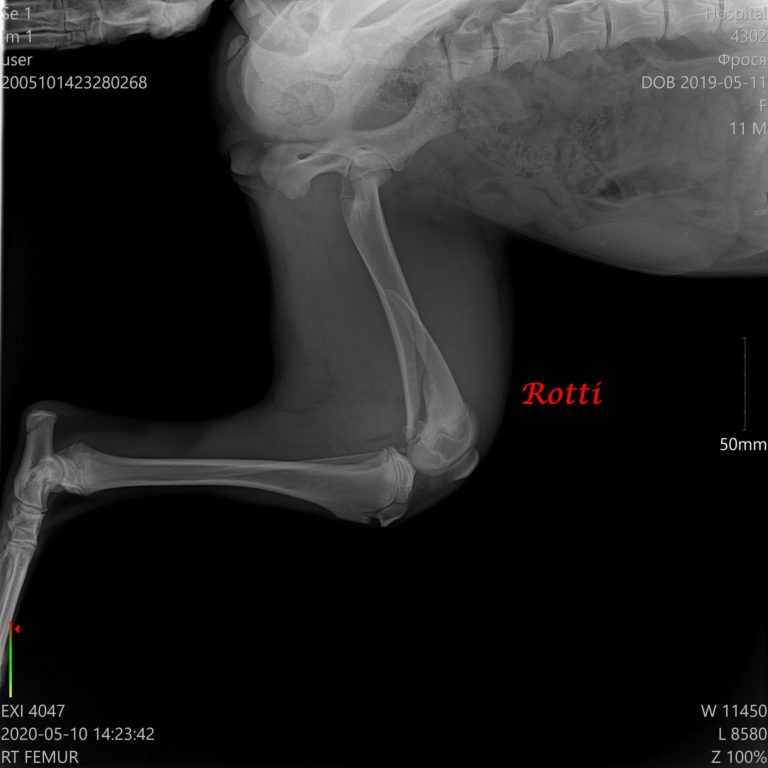

Am 10. Mai wurde sie operiert. Platten aus Metall wurden gestellt, und am 7. Juli 2020 wurden die Platten entfent. Der Bruch wurde geheilt. Rotti wurde sterilisiert.